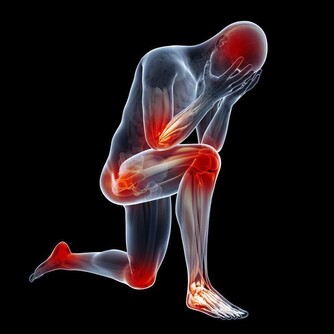

3、晨僵

有些人晨起後感覺關節僵硬,彷若被膠水粘著,但活動後會逐漸緩解,這裡註意,如果每次晨僵的時間超過30分鐘,就要懷疑是關節疾病引起的。